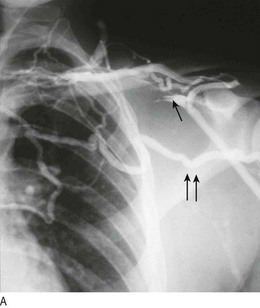

Vasospastic symptoms: Raynaud’s phenomenon is digital ischaemia induced by cold and emotion and has three phases (Fig. 6.38):

Fig. 6.38 Raynaud’s syndrome.

(A) The acute phase, showing severe blanching of the tip of one finger. (B) Primary Raynaud’s syndrome occasionally progresses to fingertip ulceration or even gangrene.

• Pallor: due to digital artery spasm and/or obstruction

• Cyanosis: due to deoxygenation of static venous blood (this phase may be absent)

Raynaud’s phenomenon may be primary (Raynaud’s disease) and due to idiopathic digital artery vasospasm, or secondary (Raynaud’s syndrome) (Box 6.38).

Patients >40 years old presenting with unilateral Raynaud’s phenomenon have underlying PAD unless proven otherwise, especially if they have risk factors (smoking, diabetes).